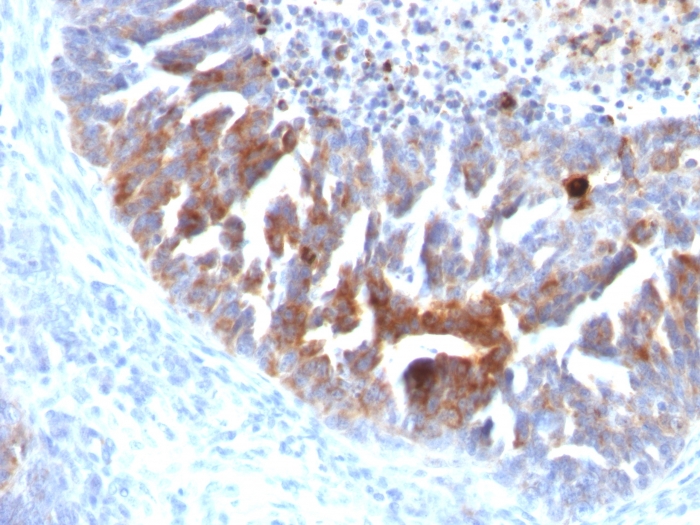

阳性对照: 肺腺癌

TAG-72是一种分子量大于1,000KDa的粘液蛋白,除分泌腺上皮外,其它正常上皮一般不表达,主要用于结肠癌、胃癌、胰腺癌、卵巢癌、内膜癌和肺癌的研究。

TAG-72抗体试剂可与TAG-72分子抗原特异性结合,含TAG-72抗体试剂的免疫组化试剂盒适用于肺癌、恶性间皮瘤、结肠癌、胃癌、胰腺癌、卵巢癌和内膜癌的精准诊断。